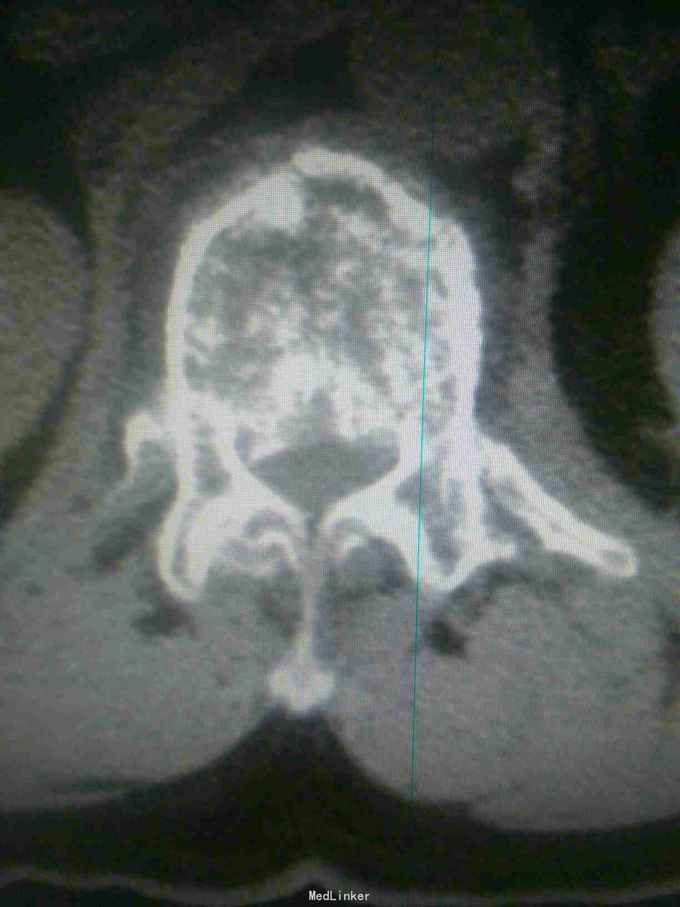

患者因高处坠落致腰痛部疼痛,双下会活动受限9小时入院。患者9小时前从3米高处坠落,腰骶部先着地,即时觉双下肢麻木,不能活动。

查体腰背部压痛,双下肢肌力0级,肌张力减低,会阴区,双下肢痛觉减低,触觉,精细觉正常,腱反射未引出,肛门反射消失,括约肌松弛。

诊断腰1,腰4椎体爆裂性骨折,腰5椎体压缩性骨折,脊髓圆锥损伤双下肢截瘫。患者入院后48小时内行了腰椎后路腰1.4椎体切开复位椎弓根钉内固定,腰1椎板切除,椎管扩大成形,横突间植骨融合术。